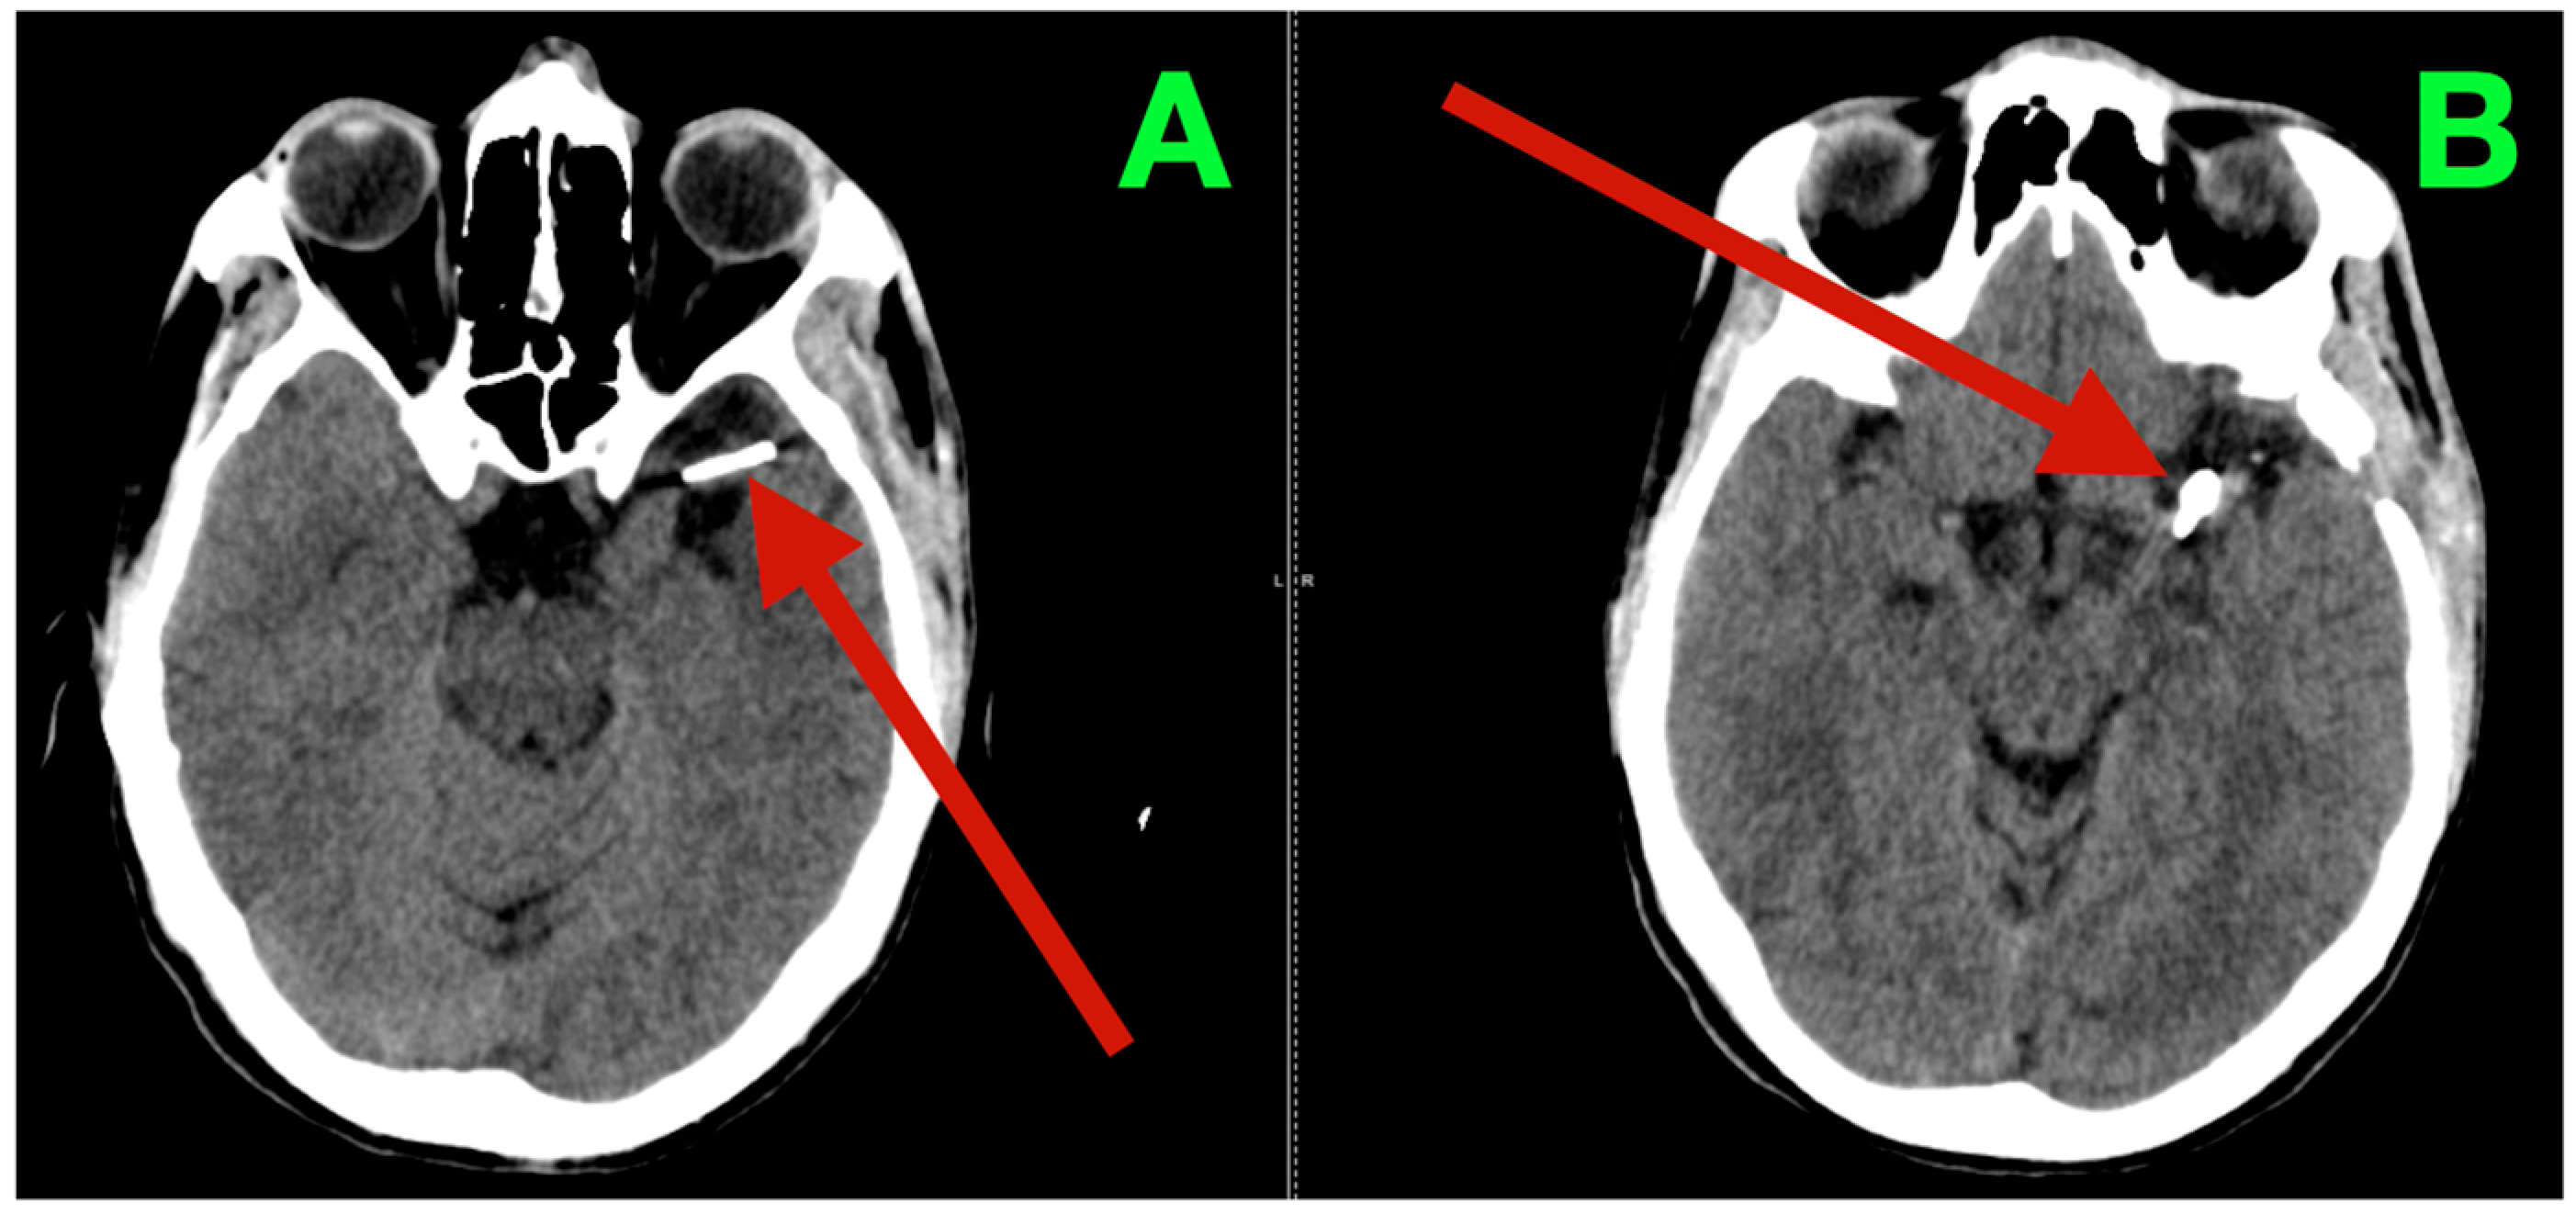

Immediate postoperative neuroimaging was not obtained, consistent with the institutional protocol in neurologically stable patients after uncomplicated microsurgical aneurysm clipping. Predefined triggers for urgent imaging—any new focal deficit, sustained escalation of headache, decline in level of consciousness, or refractory hypertension—did not occur during inpatient monitoring. The patient was discharged on postoperative day three with instructions regarding blood pressure control, wound care, graded activity progression, and scheduled outpatient visits at two weeks, six weeks, and three months. At interval clinic assessments, he reported complete resolution of the preoperative vascular-pattern headaches, absence of exertional provocation, and restored confidence in balance and sustained fine-motor endurance during overhead tasks. The neurological examination remained normal and unchanged from the inpatient baseline. At three months, non-contrast cranial CT (Figure 3) demonstrated the expected clip artifacts at the MCA bifurcation and proximal M1 with preserved parenchymal attenuation throughout the superior division territory and within the internal capsule and dorsal basal ganglia, without encephalomalacia, hydrocephalus, or extra-axial collection, radiologically corroborating durable exclusion of both aneurysms with intact branch and perforator perfusion. Functional outcomes were congruent with the radiology and clinical course: the patient met criteria for complete independence with a modified Rankin Scale score of 0 and National Institutes of Health Stroke Scale (NIHSS) of 0 at discharge and again at the three-month follow-up.

Figure 3.

Three-month postoperative non-contrast cranial CT. (A) Axial non-contrast CT at the level of the left MCA bifurcation/insular apex, showing the expected clip artifact centered on the bifurcation–proximal M1 complex, with preserved cortical ribbon along the opercular–insular corridor, normal attenuation of the internal capsule and dorsal basal ganglia, and no peri-clip hypodensity, hemorrhage, or mass effect. (B) Axial non-contrast CT at a slightly higher level through the superior division territory, demonstrating intact suprasylvian cortex and corona radiata without encephalomalacia or gliotic change. Ventricles and basal cisterns are normal in size and configuration, midline is preserved, and there is no extra-axial collection.

The durable resolution of preoperative micro-asymmetries, together with structurally preserved dominant-hemisphere parenchyma on the three-month CT, supports effective clip reconstruction with maintained superior-division branch flow and uncompromised lenticulostriate perfusion.